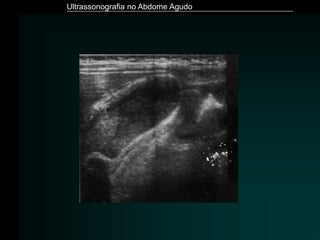

• #14 .

• #55 LEIOMIOMA SEM FLUXO AO DOPPLER – TORÇÃO OU DEGENERAÇÃO PACIENTE GESTANTE CONDUTA EXPECTANTE COM SINTOMÁTICOS PARA A DOR – EVOLUIU BEM.